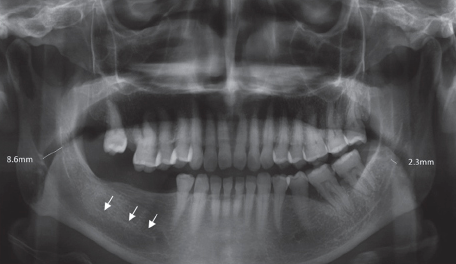

Mental foramen

dark circle near lower premolars

Mandibular canal

dark horizontal line in mandible